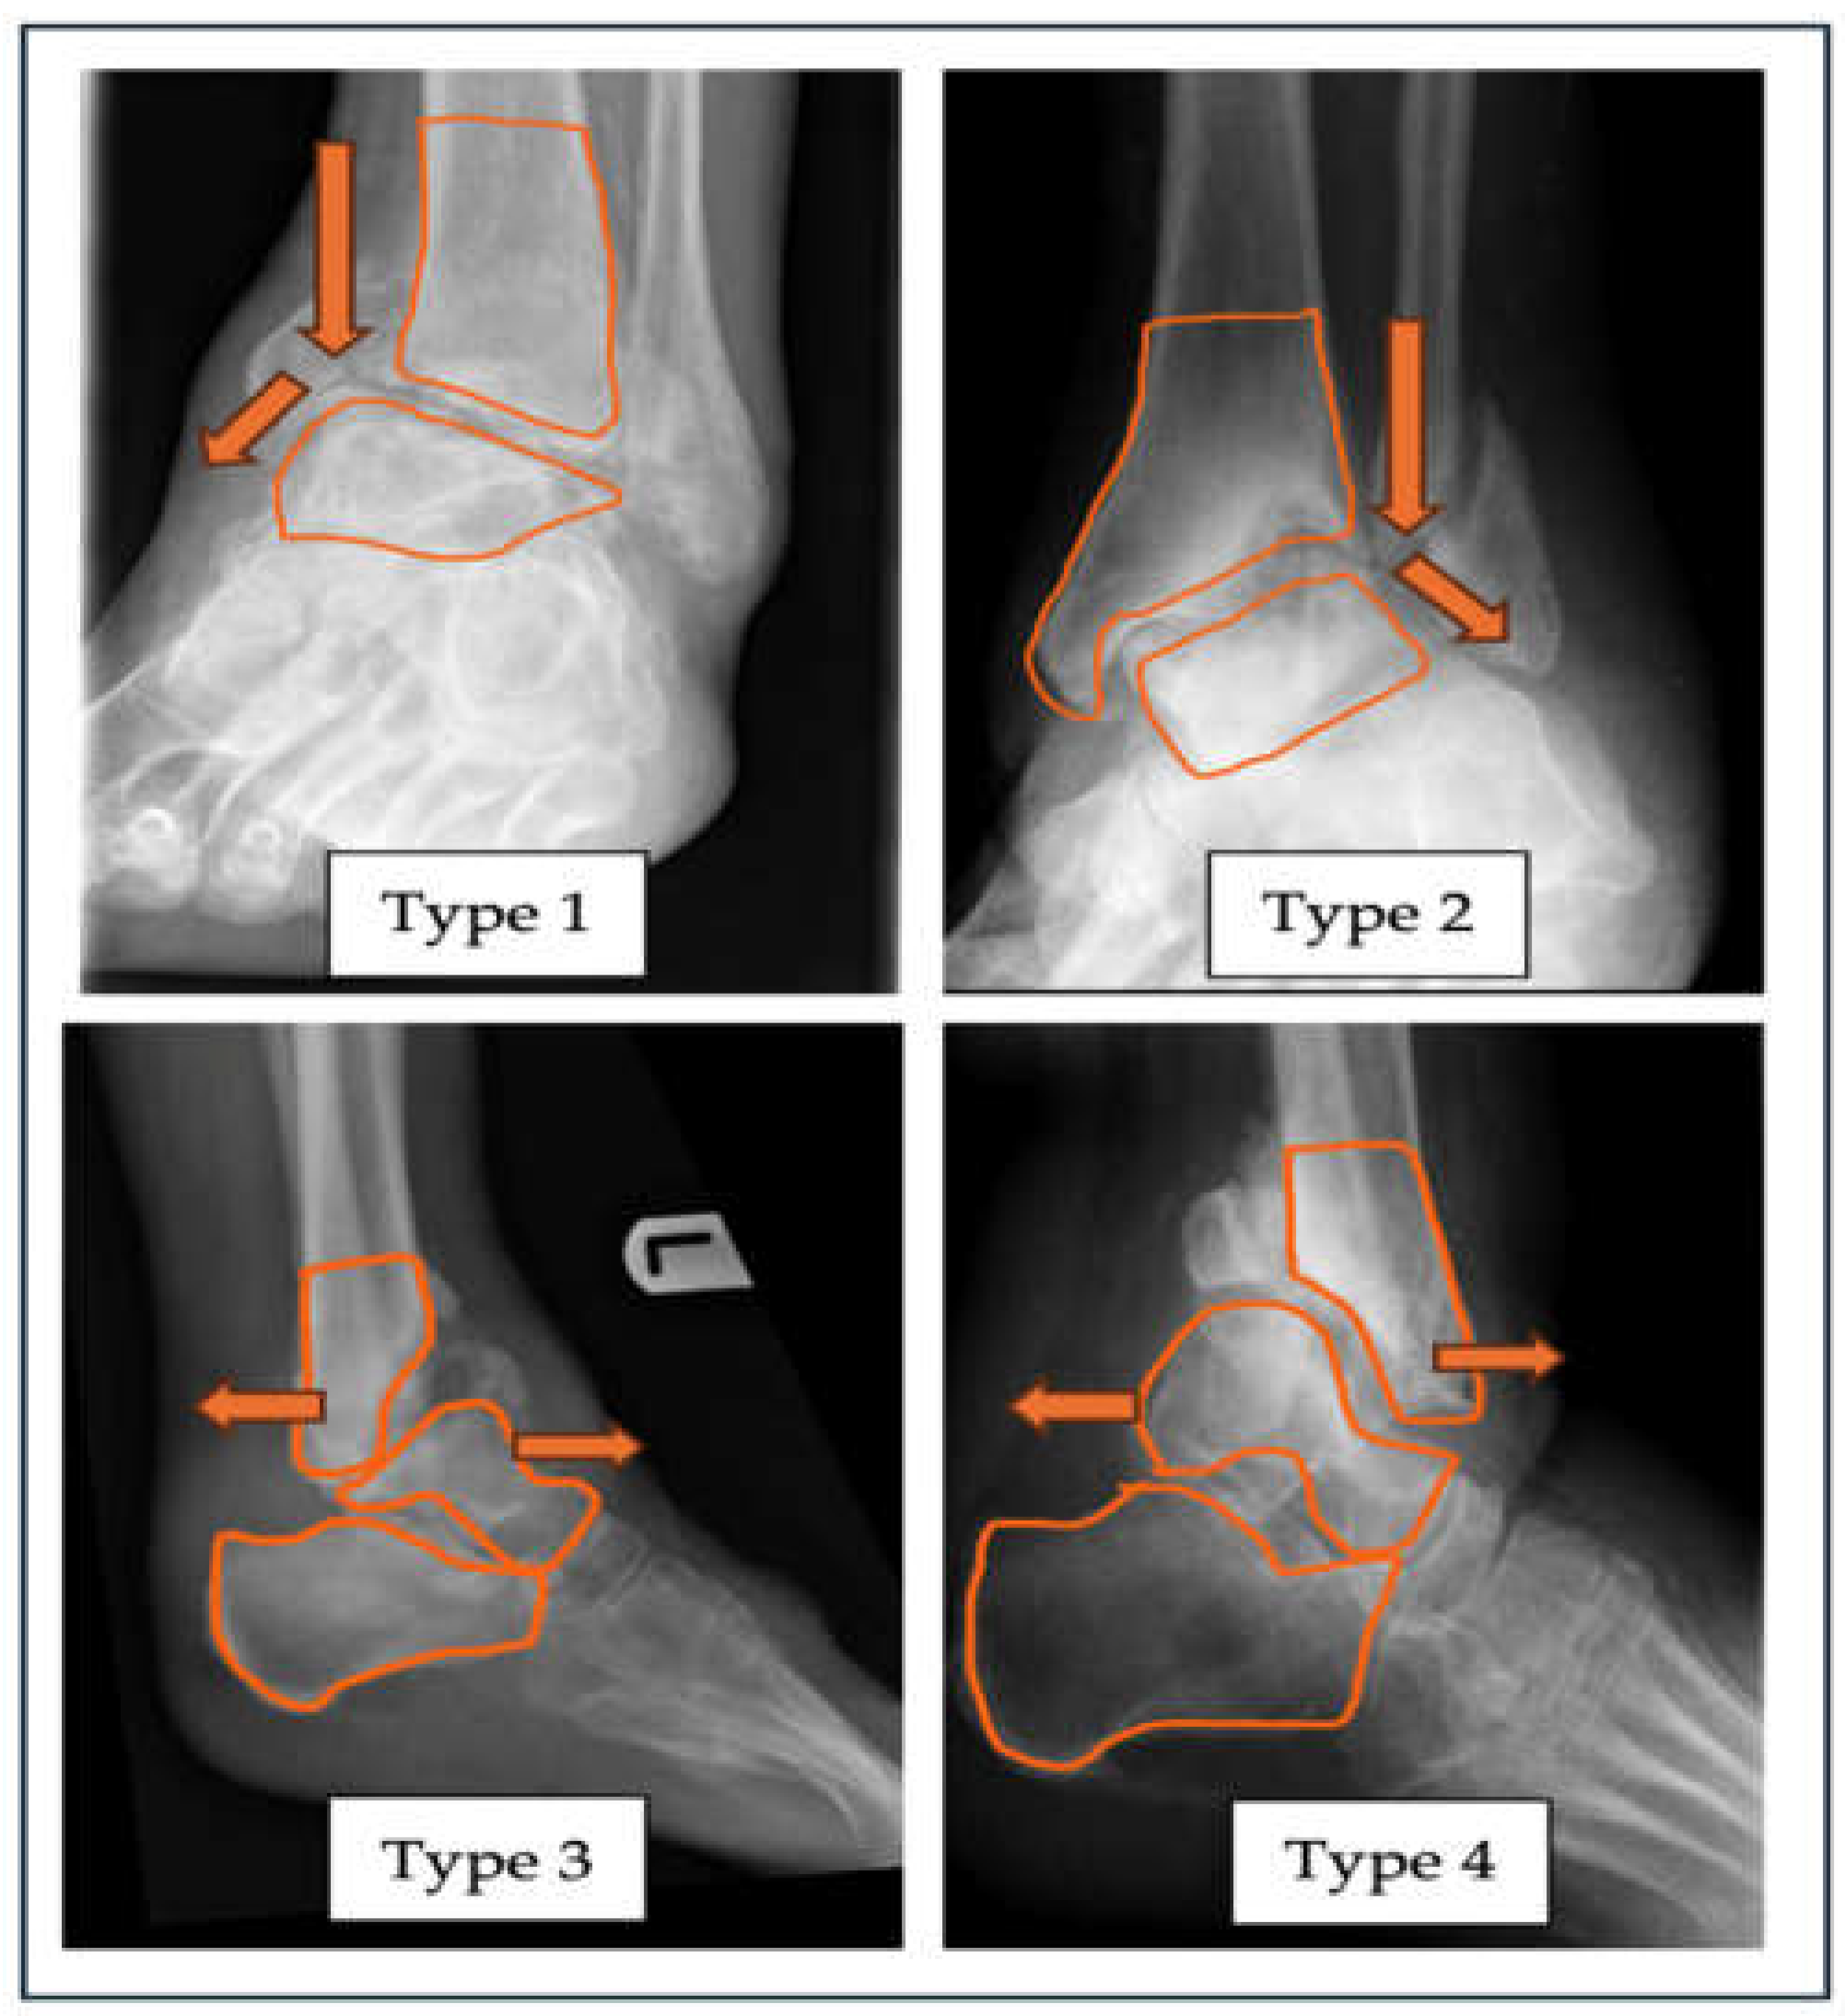

| “A” - Alignment | Varus (Type 1) |

Valgus (Type 2) |

Anterior (Type 3) |

Posterior (Type 4) |

| Neutral – label as Type N Combined Label as Type 5 |